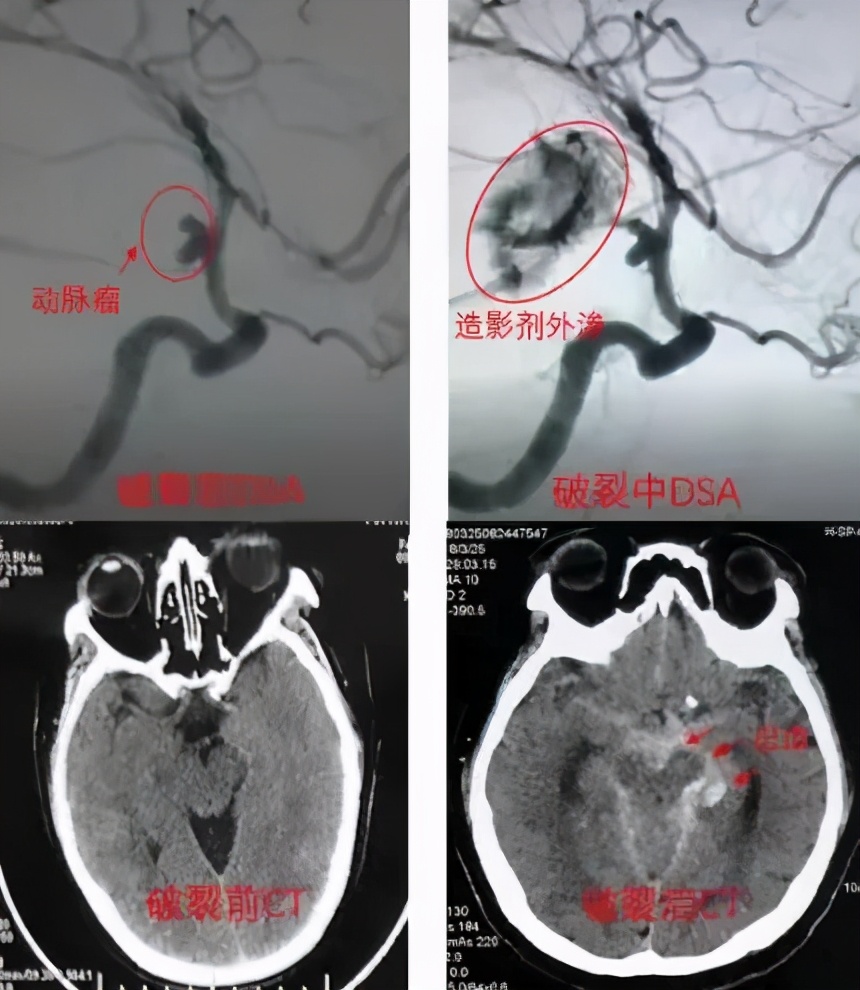

55岁李先生原本是位健康的公司高管,日前突然发生剧烈头痛、呈爆炸性,伴有呕吐、颈部僵硬等症状,送至医院时肢体无力、反应迟缓,已呈现昏迷状态。头部断层扫描呈现为头部“自发性蛛网膜下腔出血”,CTA结果提示为大脑前交通动脉瘤。幸好,经医师进行紧急介入手术,用弹簧圈成功完全填塞动脉瘤,有效地防止了动脉瘤再度破裂出血,术后经药物及康复治疗李先生恢复良好,出院时四肢活动自如,没有留下任何后遗症。

临床上,蛛网膜下腔出血分为外伤性和自发性两大类。其中,自发性蛛网膜下腔出血是一种常见且致死率极高的疾病,主要以颅内动脉瘤(80%)和脑血管畸形最为常见,其他病因还有高血压性动脉粥样硬化引起的动脉破裂、烟雾病、各种感染引起的脑动脉炎、肿瘤破坏血管等。其中以颅内动脉瘤最为凶险!!!

不过这个病的危害在于:长期隐藏不破则矣,一旦破裂,会导致严重的出血,威胁生命。1/3患者在30天内死亡,1/3患者幸存,但神经功能丧失(残疾),1/3患者康复。动脉瘤破裂一次后,出现再次破裂的机率非常高,不良预后的发生率高达60-70%,因此发生动脉瘤破裂时,一定要即时送医处理。因此本病又被称为”不定时*弹炸**“。